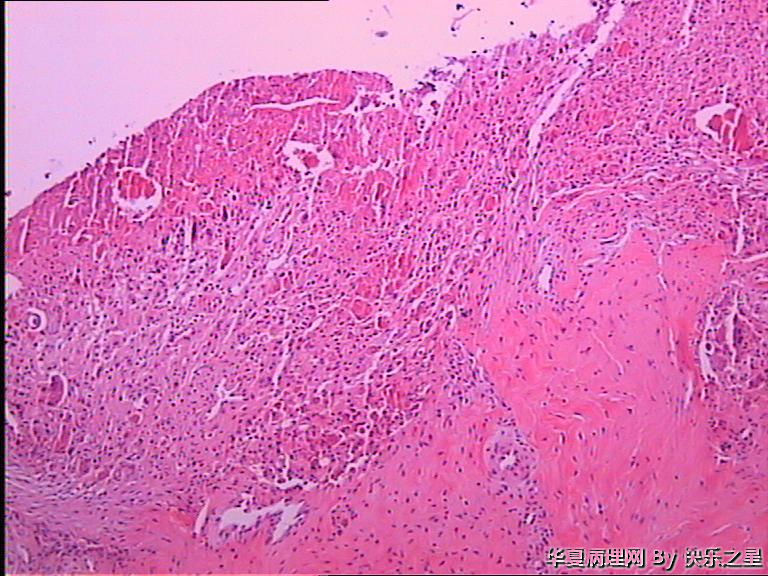

女,32岁,右足第一趾骨头疼痛5天。

肉芽肿性炎伴砂粒体形成。可能为深部真菌感染引起。异物性肉芽肿和腱鞘巨细胞瘤也可以这样。总之是良性瘤样病变。

痛风石?